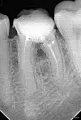

Прошла неделя после пломбирования каналов. Зуб реагирует на накусывание, ноющие боли. Врач по снимку говорит, что все в порядке, нужно ждать еще неделю. Зуб под коронкой. Прошу Вас рассмотреть снимок и дать оценку состояния зуба.

Комментарий №161250

• На этом снимке ничего катастрофического я не вижу, но считаю, что лучше сделать К/Т и убедиться в этом.